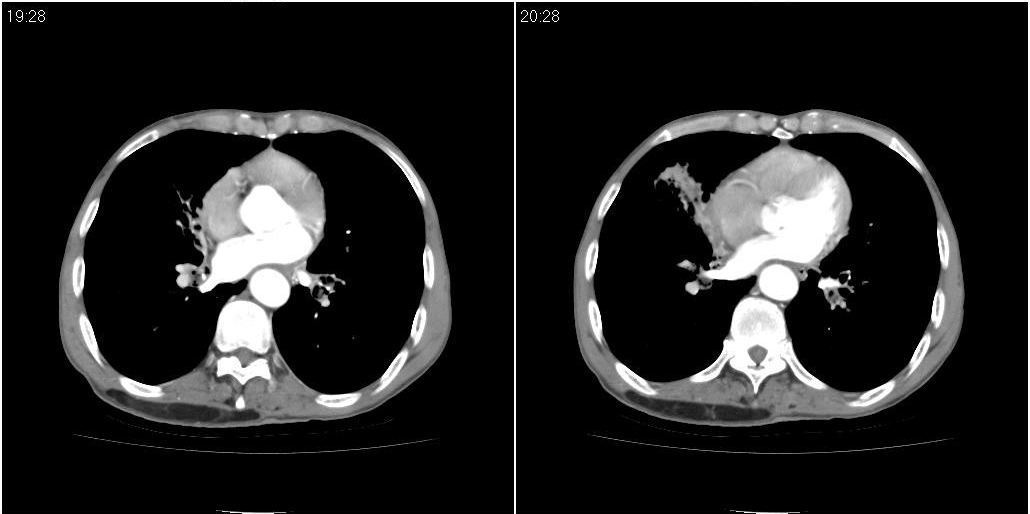

标题: CT25416:男性,70岁。胸片发现右下肺斑片状阴影

以下是ct检查的情况:

标题: ct增强:

右肺中叶阻塞性不张及肺炎,高度怀疑支气管占位,建议纤支镜检查!

1)右肺中叶慢性炎症并支气管扩张,节段性肺不张。2)两肺下叶支气管扩张。

1)右肺中叶慢性炎症并支气管扩张,节段性肺不张。2)左肺下叶支气管扩张